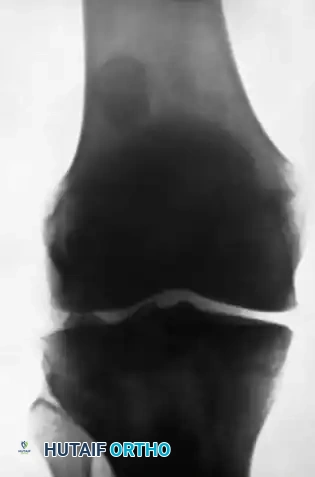

Figures A and B: Lateral and Anteroposterior radiographs demonstrating a large loose body in the lateral portion of the suprapatellar pouch, with a smaller body in the posterolateral compartment. Note: The small fragment of bone opposite the posterior surface of the lateral femoral condyle is the fabella (a normal sesamoid bone in the lateral head of the gastrocnemius muscle), which must not be mistaken for a loose body.